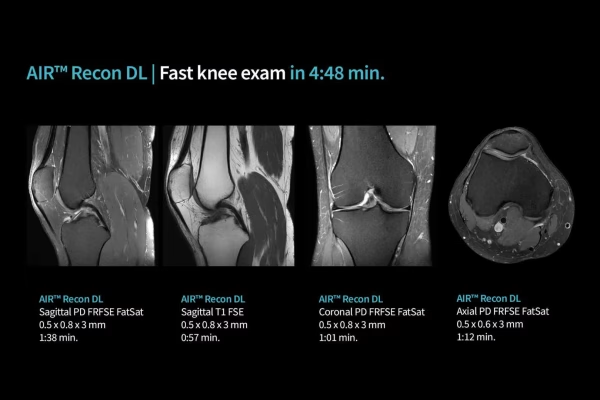

IRM GE Signa Explorer 1.5T